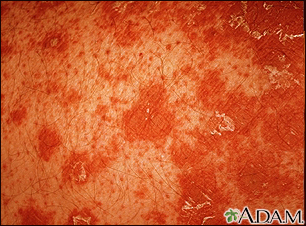

Primer plano de la pitiriasis rubra pilaris